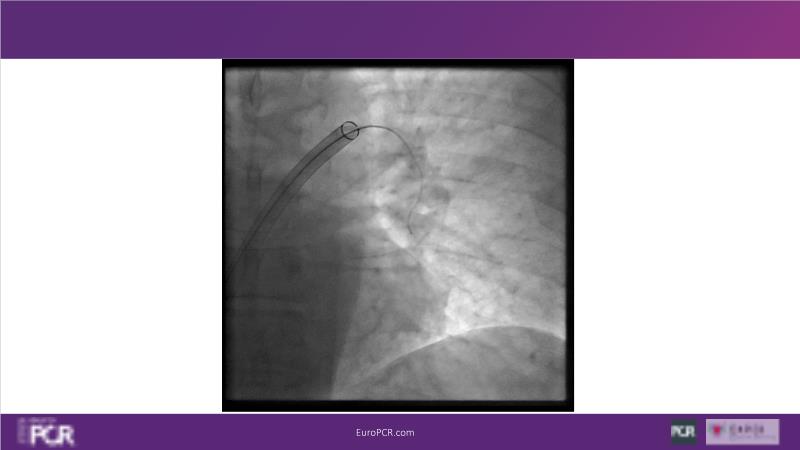

Why mechanical thrombectomy should be considered in the management of acute pulmonary embolism

In this EuroPCR 2024 session, study the case of a patient with high-risk pulmonary embolism and another with intermediate to high-risk pulmonary embolism, delve into discussions on clinical evidence for mechanical thrombectomy in pulmonary embolism, acquire skills to evaluate eligibility for mechanical thrombectomy, and learn how to integrate such technique in local pulmonary embolism patient pathway.